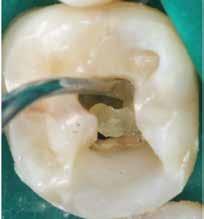

2. ábra: A hozzáférési nyílás kialakítása során túlzott mértékű ép foganyag eltávolítása történt mesiobukkális és apikális irányba.

– 3. ábra: A visszamaradt nagy méretű pulpakő teljes mértékben elzárja a palatinális csatornabemenetet. – 4. ábra: A gyökértömés behelyezése előtt látható állapot. A csatornák feltágítása és tisztítása befejeződött.

mány kritikus mértékű strukturális károsodását is okozhatják (1–5. ábrák). Egészen a közelmúltig annak a fontosságát hangsúlyozták, hogy a trepanációs nyílások kiterjedésének kellően nagynak kell lennie ahhoz, hogy a kézi és gépi eszközök számára közvetlen, egyenes vonalú hozzáférést biztosítsanak a gyökércsatornákba való behatolás során. Az utóbbi években viszont a minimálinvazív módon kialakított trepanációs nyílások (ultrakonzervatív üregek, ninja hozzáférés stb. …) [4] előnyeire fókuszáló szemléletek kaptak egyre nagyobb nyilvánosságot.